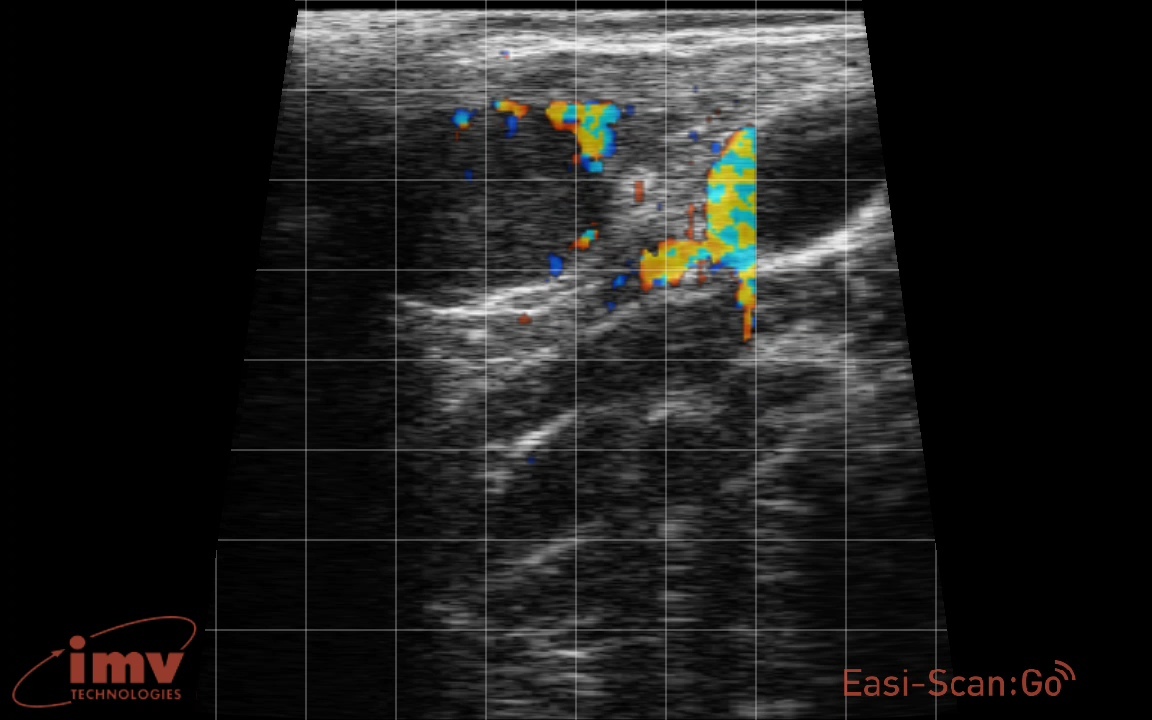

Стельная корова

Сохранение васкуляризации жёлтого тела при стельности на 20-й день основано на действии хорионического гонадотропина, который предотвращает регрессию жёлтого тела, поддерживает его функциональную активность, стимулирует кровоснабжение и подавляет процессы разрушения.

Механизм действия хорионического гонадотропина включает блокировку процессов инволюции, активацию выработки прогестерона, поддержание нормальной работы сосудов и предотвращение гибели клеток жёлтого тела. Эти эффекты обеспечивают высокую васкуляризацию, необходимую для выработки прогестерона, поддержания стельности и обеспечения кровоснабжения.